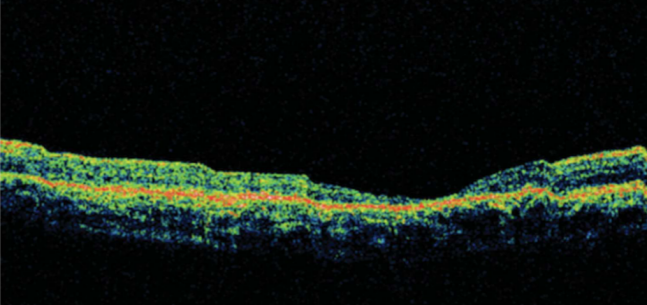

专科检查:右眼最佳矫正视力为20/100;左眼最佳矫正视力为20/40。眼前节检查无异常。两只眼睛的眼底检查均显示黄斑部有黄斑牛眼征,环形古铜色区域外有一圈紫红色(图 1 , 2)[1]

图1

遇到这样双眼黄斑牛眼征,首先考虑遗传性疾病,OCT和电生理检查肯定是少不了的。该患儿双眼的OCT扫描显示黄斑中心凹变薄,右眼更严重,感光器萎缩,RPE反射率增加(图3和图4)[1]。ERG显示熄灭型,而暗适应基本正常。如果考虑色素变性,该患儿没有描述夜盲症状,眼底彩照也没发现视网膜色素改变,仅仅是黄斑区牛眼征。

双眼OCT显示(图3,4)患者的中心凹变薄和感光细胞发生萎缩。该患儿在停止口服药物后,视力仍在进行性下降,推测持续升高的血清铁蛋白对视力造成更大的伤害。